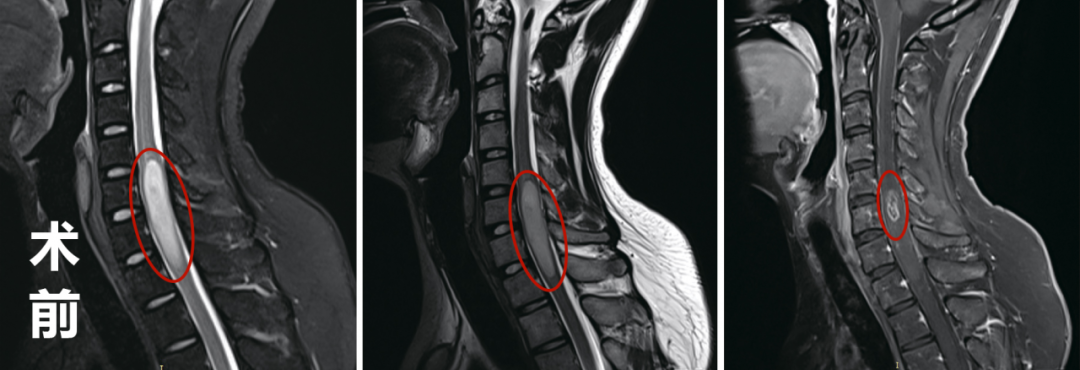

教授还安排我做了MRI,他说尽快对比术前后的影像才能判断切除情况,患者顺利地结束手术并不是目的,高切除率以及术后没有神经功能损伤才是。教授还特意跟我说,我可以恢复正常生活。

术前术后影像对比显示:脊髓内星形细胞瘤的瘤体强化部分被完整切除,肿胀效应减轻